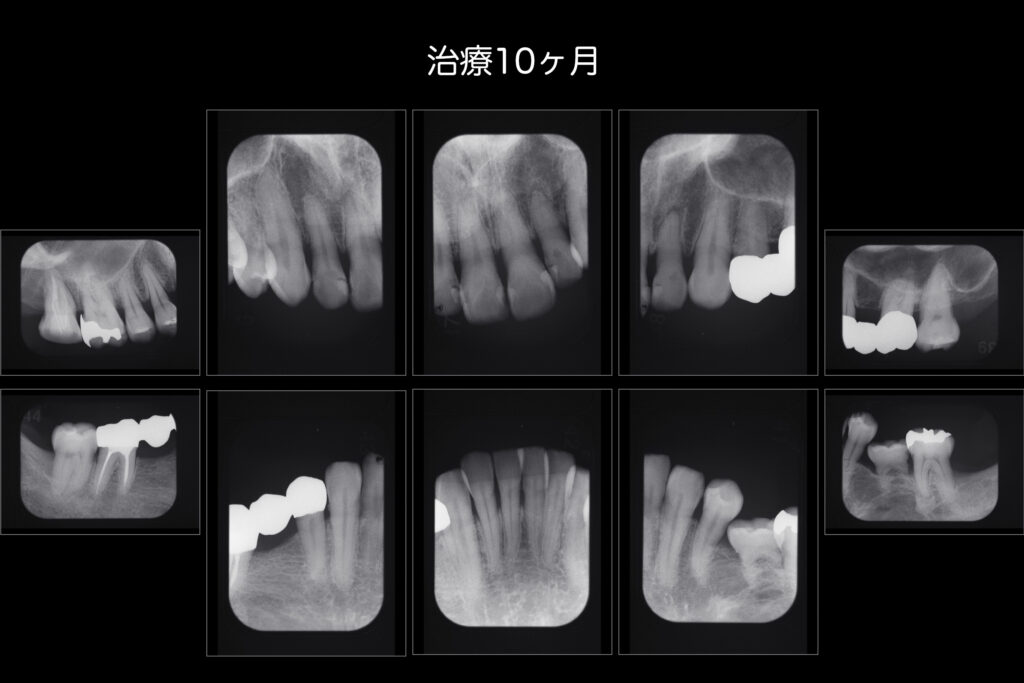

先日は就業時間内に時間を取りより患者様へ寄り添った歯科診療を行えるよう月一回の院内勉強会を行いました。

演者は歯科衛生士Sさんによる歯周基本治療の成果や経過の臨床発表でした。

歯周外科(歯ぐきを切って外科的に歯石を取ったりすること)を行わず、患者様と2人3脚で改善している様は

担当衛生士S(全力サポート衛生士N)はもちろん患者様自身のセルフケアの劇的向上によるものです。

今後もより良い経過が続くよう寄り添って参ります。

できる限り自分の歯で人生を楽しみたい方は是非ご相談ください。